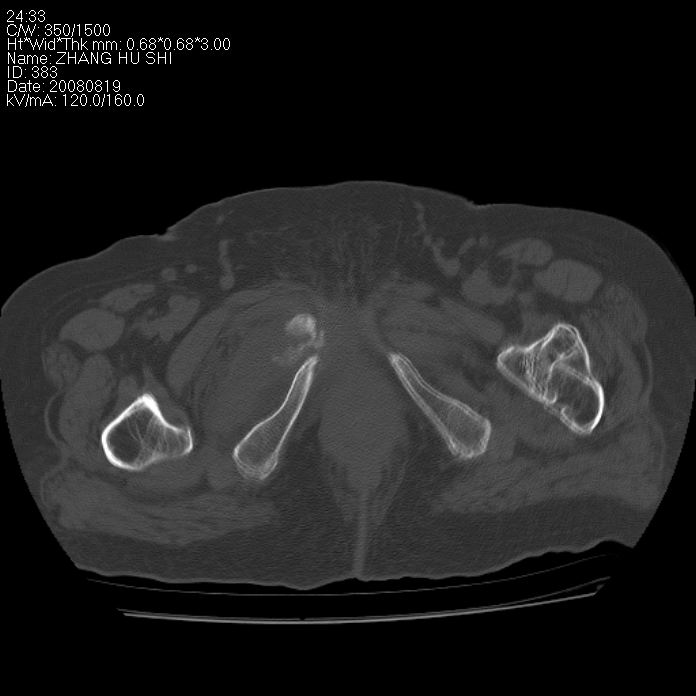

标题: CT15287:女 93岁 右髋关节疼痛 原左侧粗隆间骨折 CT发现右耻 [打印本页]

标题: CT15287:女 93岁 右髋关节疼痛 原左侧粗隆间骨折 CT发现右耻

支持转移并周围软组织侵犯右闭孔内肌侵犯,但tb不能完全除外。